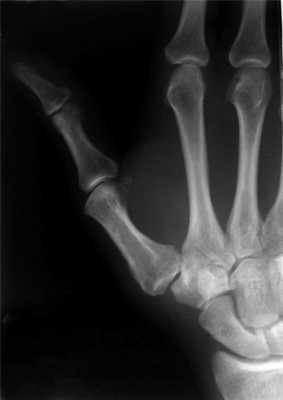

Пример операции доктора Валеева по восстановлению после перелома первой пястной кости:

Перелом основания I пястной кости. Характерная травма для боксеров и бойцов MMA. Различают перелом Беннета — отрыв участка основания первой пястной кости, который удерживается связками, с одновременным вывихом ее большей части в запястно-пястном суставе. Перелом Роландо — многооскольчатый переломовывих I пястной кости. Обе травмы проявляются болью, деформацией и отечностью в области “анатомической табакерки” — области под основанием первого пальца — с усилением боли при движении, попытке сжать кулак. Диагностика осуществляется с учетом жалоб, данных анамнеза травмы, осмотра области повреждения и рентгенографии кисти. Лечат переломы Беннета и Роландо хирургическим путем с применением остеосинтеза — восстановления целостности кости путем фиксации отломков металлическими спицами, штифтами или пластинами.